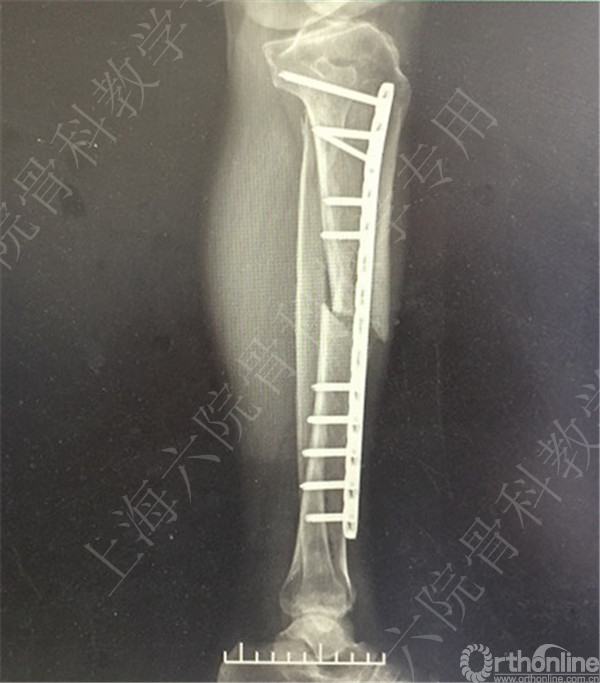

患者复查,X线摄片示:骨折对位对线差,左胫骨立线欠佳,成角。

患者择期行左胫骨切开复位内固定术+髂骨异体骨植骨。

术后X线摄片示:骨折对位对线可,内固定牢靠,左胫骨对线可。

医方第一次跟换内固定术中,未纠正左胫骨立线,骨折对位对线差,未纠正成角,导致术后内固定失效,骨折成角变大。医方存在手术方式不当,手术操作不当,术后并发症观察、处理不当,对疾病评估不足,告知缺陷等过失。